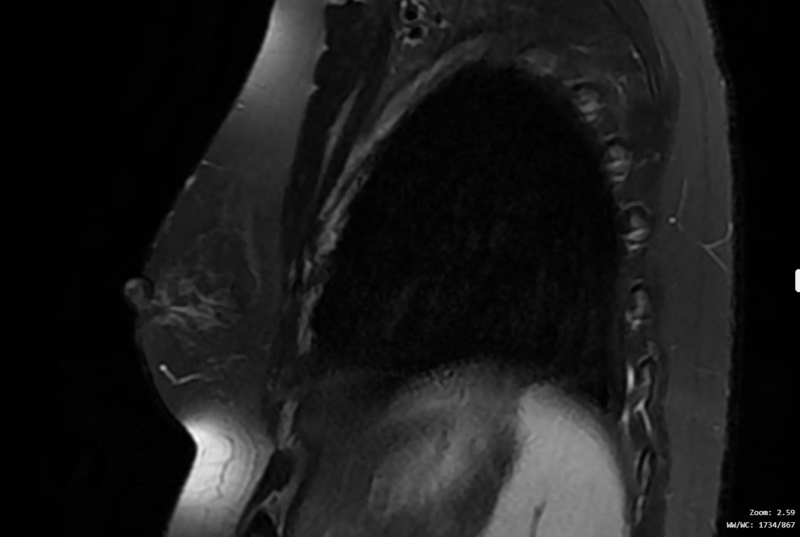

Imagen de una resonancia magnética de mama. León Scanner.